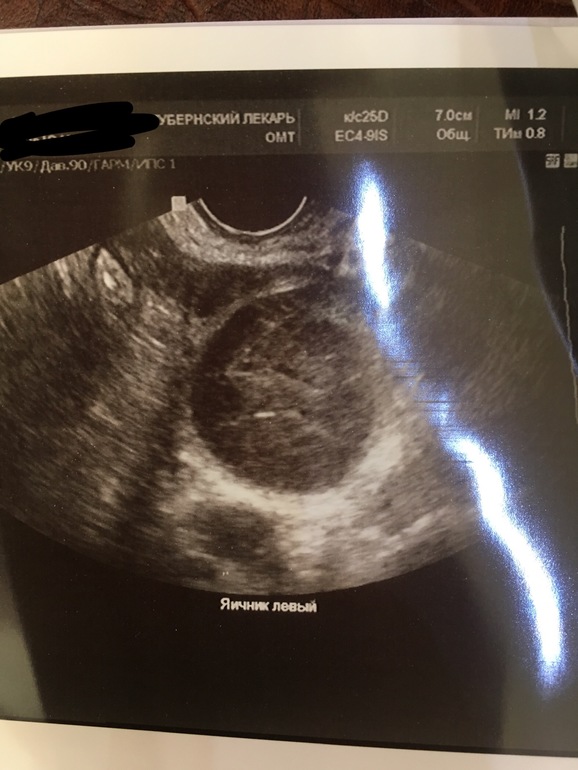

Там же в заключении написано, что подозрение на эндомеирмоидную кисту и плюс второй яичник мультифолликулярный. В теле матки подозрение на аденомиоз и в шейке матки какая то киста. Вам к врачу нужно, это не овуляция.

Эндометриоидная киста*

Ну это пока все подозрение, эндометриоз ставится только гистологически, если Вам до этого не ставили этот диагноз, то скорее всего пока наблюдать врач скажет, может они функциональные.

Вам к врачу надо. На вид МФЯ и полипы цервикального канала.